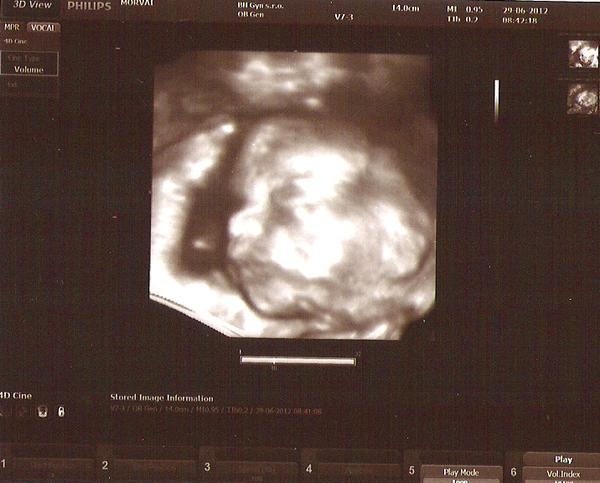

S chlapcekom je vsetko v poriadku, je krasnucky. Kuk na fotku.... 🙂 O 2 tyzdne ideme s manzelom na 4D a potom uz budeme mat aj 45 minutovy DVD... uz sa neviem dockat.... 🙂